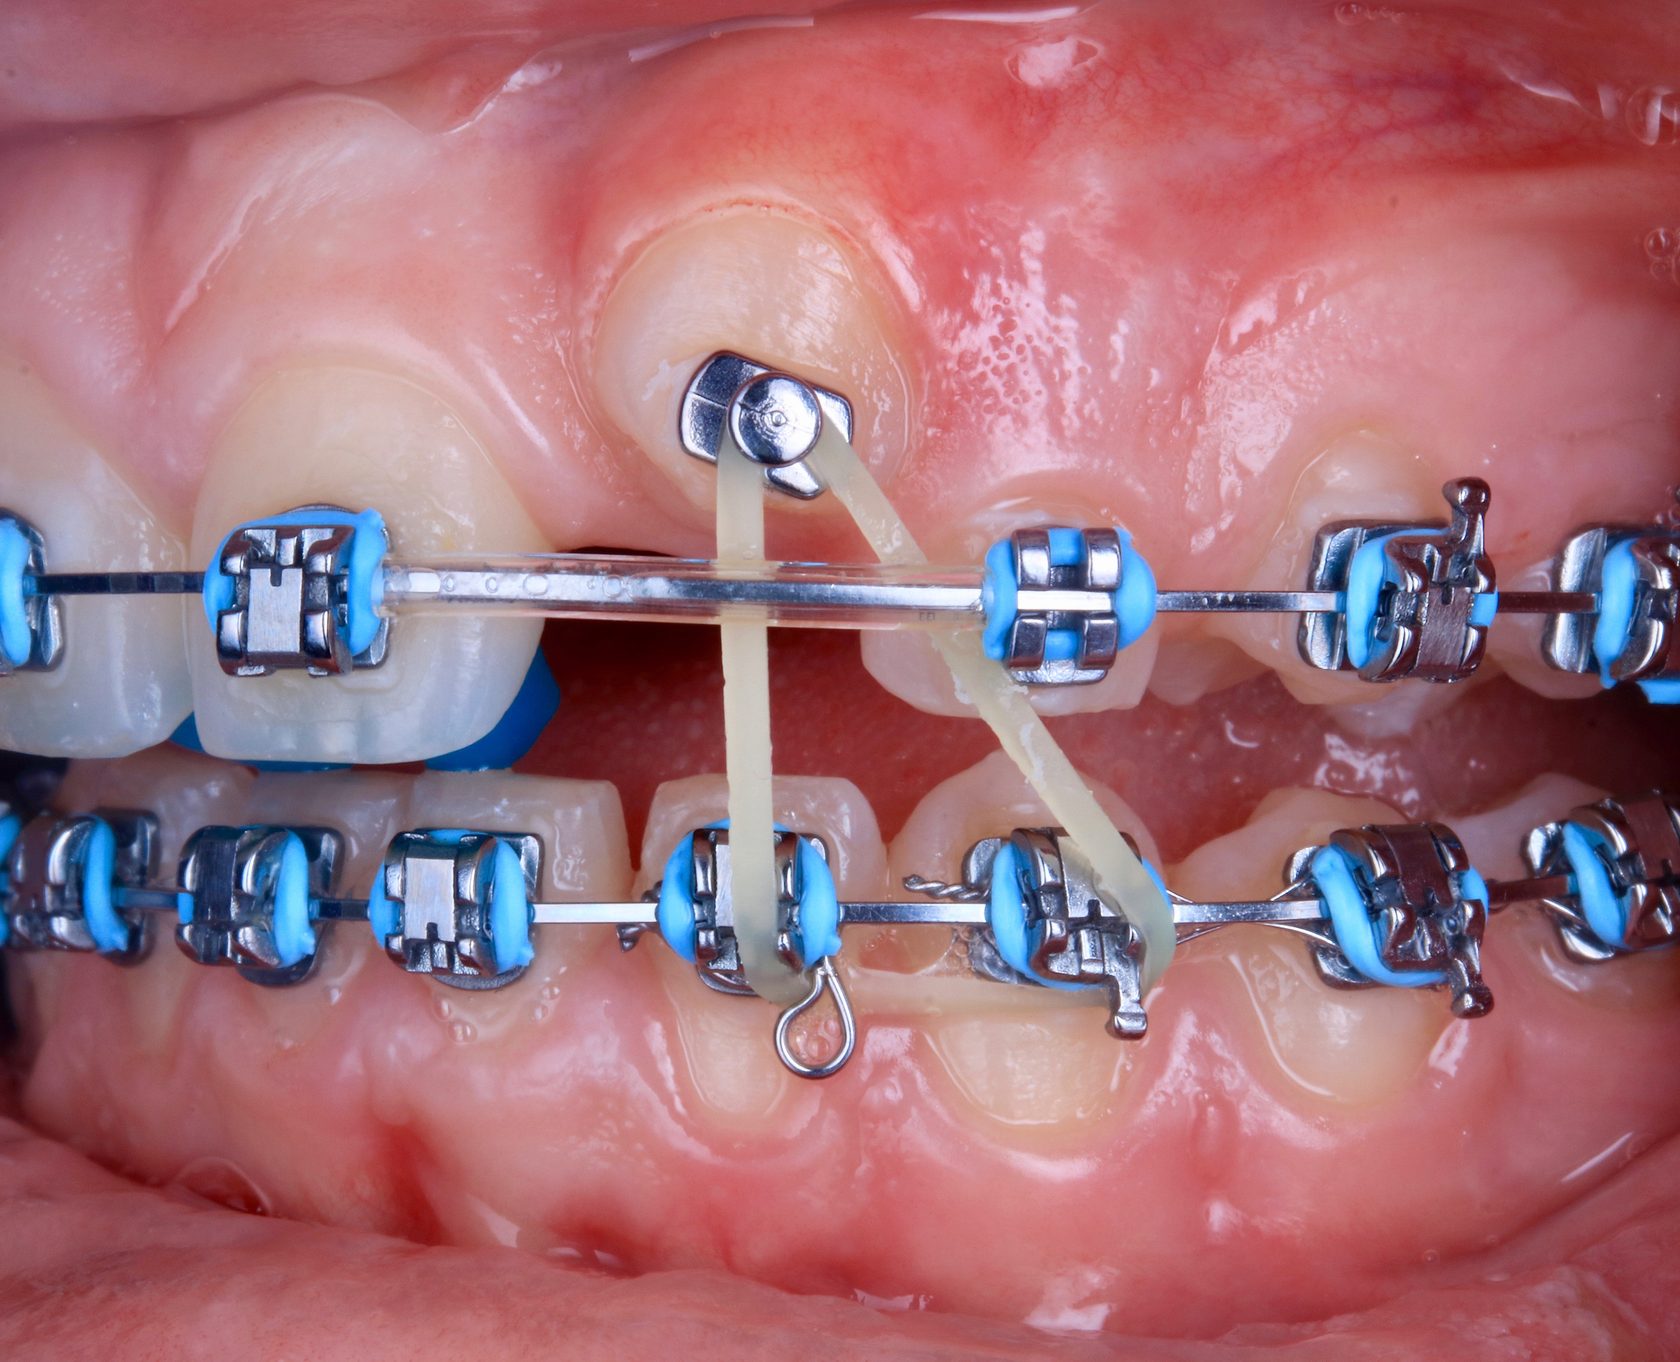

Дентальная галерея: ретинированный зуб клык и его лечение

Раздел: Компас решений